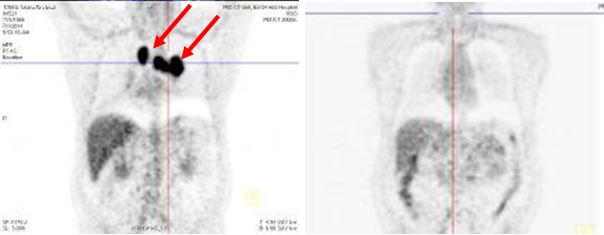

CHỤP PET/CT TOÀN THÂN

Hình ảnh khối u rốn u rốn phổi trái KT 4x4,5cm tăng hấp thu FDG mạnh, SUV=12,3.

Di căn hạch trung thất và hạch rốn phổi hai bên kích thước lớn nhất 2,5x3,6cm, SUV=6,8.

Di căn hạch trung thất tăng hấp thu FDG, nốt mờ thùy trên phổi trái tăng hấp thu FDG

Bệnh nhân:chụp PET/CT lần 2 đánh giá sau 6 chu kỳ hóa chất (có đối chiếu với lần chụp trước khi điều trị).

Trước và sau điều trị hóa chất 6 chu kỳ